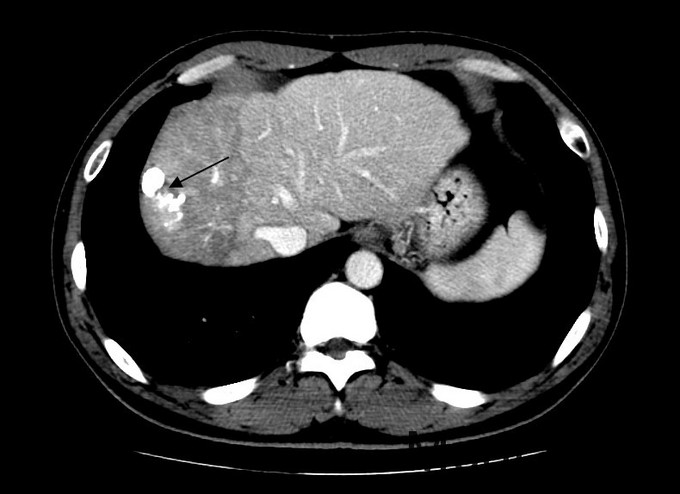

查体:血压131/76mmHg.神志清晰。颜色正常,无皮疹及瘀点。无肝掌。浅表淋巴结未触及肿大。眼睑无水肿,巩膜无黄染,结膜正常。双侧瞳孔等大正圆。心肺听诊无异常。腹型平坦,无腹壁静脉曲张,未见胃肠型及蠕动波,无瘢痕,脐部正常。腹软,无压痛及反跳痛,无腹肌紧张,未触及包块。肝未触及,Murphy征阴性,脾未触及,无触痛,肾未触及。无肝区叩击痛,肝上界位于右锁中线第6肋间,无肾区叩击痛,无脾区叩击痛。移动性浊音阴性。四肢活动自如,无双下肢水肿。扑翼样震颤阴性。 化验:血细胞分析:白细胞计数 3.9 10^9/L、血小板计数 121.0 10^9/L、血红蛋白 134 g/L,肝功酶谱:丙氨酸氨基转移酶 50 U/L、总蛋白 73.5 g/L、白蛋白 42.4 g/L、总胆红素 13.3 umol/L,凝血五项:凝血酶原百分活动度 76.4 %,丙肝抗体 27.90 S/CO,丙肝病毒RNA定量 <1.0E+03 IU/ml,甲胎蛋白 1296.00 ng/mL, 肝脏增强CT示:肝硬化,脾大,腹水少量。肝癌介入手术治疗后,S8段强化灶。肝右叶灌注异常,考虑门脉右前支受侵。

诊断:1丙肝肝硬化 活动期 代偿期 HCC术后 2高血压 治疗:入院后休息,低脂低盐软食。肿瘤辅助治疗,静点苦参碱。抗病毒,口服daclatasvir和sofosbuvir联合利巴韦林。控制血压,口服替米沙坦抗纤维化。对于S8段强化灶,考虑疾病进展,再行TACE治疗。

术后:查体:眼睑无水肿,巩膜无黄染。心肺听诊无异常。腹软,无压痛及反跳痛,无腹肌紧张,未触及包块。肝未触及,Murphy征阴性,脾未触及,无触痛,肾未触及。无肝区叩击痛,无肾区叩击痛,无脾区叩击痛。移动性浊音阴性。 化验:血细胞分析:白细胞计数 8.8 10^9/L、红细胞计数 4.04 10^12/L、血小板计数 113.0 10^9/L、血红蛋白 131 g/L、中性粒细胞百分比 88.4 %,肝功酶谱:丙氨酸氨基转移酶 258 U/L、天门冬氨酸氨基转移酶 245 U/L、白蛋白 34.1 g/L、总胆红素 29.4 umol/L,凝血五项:凝血酶原时间 12.2 秒,C反应蛋白测定:C反应蛋白 1.50 mg/L,降钙素原检测:降钙素原测定 0.08 ng/ml,甲胎蛋白测定:甲胎蛋白 1294.00 ng/mL。 患者6周前行一次TACE治疗,本次为病情进展,提示我们TACE术后必须加强随访,定期复查CT。